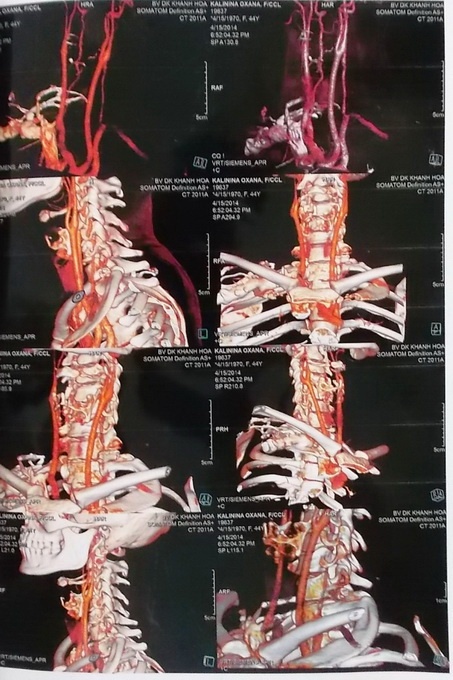

Ảnh chụp MSCT vùng bị chấn thương cho thấy có dị vật dài 39 mm đâm xuyên qua lỗ liên hợp C7 vào ống sống bên trái. Chụp MRI cho thấy dị vật 39mm x 6mm xuyên qua gần hết tủy, lồi đĩa đệm C5/6 ra sau trung tâm.

| Ảnh chụp MSCT vùng cột sống cổ bị chấn thương. |